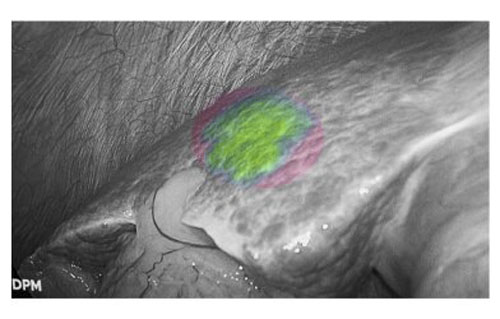

肝癌患者多合并肝硬化背景,而腹腔镜手术因缺乏触觉反馈,致使术者在微创条件下难以识别隐匿性病灶。吲哚菁绿(ICG)荧光显影技术通过术前静脉注射造影剂,可精准定位3毫米的原发性肝癌和肝转移癌。该技术有效弥补了腹腔镜肝胆手术中触觉反馈缺失的固有缺陷,为微创精准外科提供了重要技术支撑。

荧光显影技术,可精确显示肝内隐匿病灶

患者肝右后叶肝癌,根据三维重建精准阻断右后肝蒂,获得缺血线后进行荧光反染,显示肝脏切面的荧光和非荧光界面,助力解剖性肝右后区切除。